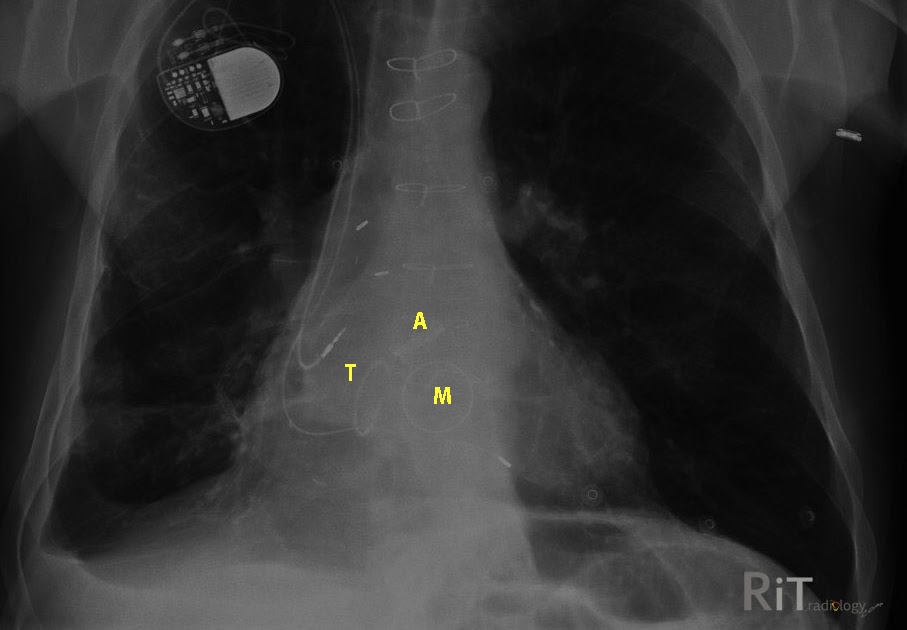

RiT radiology Anatomic Position of Heart Valves Valves Radiograph it is best to list the four valves in the order which blood travels through the heart: The aortic and pulmonary valves are above a. the chest radiograph can localize the great majority of valve prostheses to the aortic, mitral, or tricuspid positions, and it can usually. the heart valves are best determined on a lateral radiograph.. Valves Radiograph.